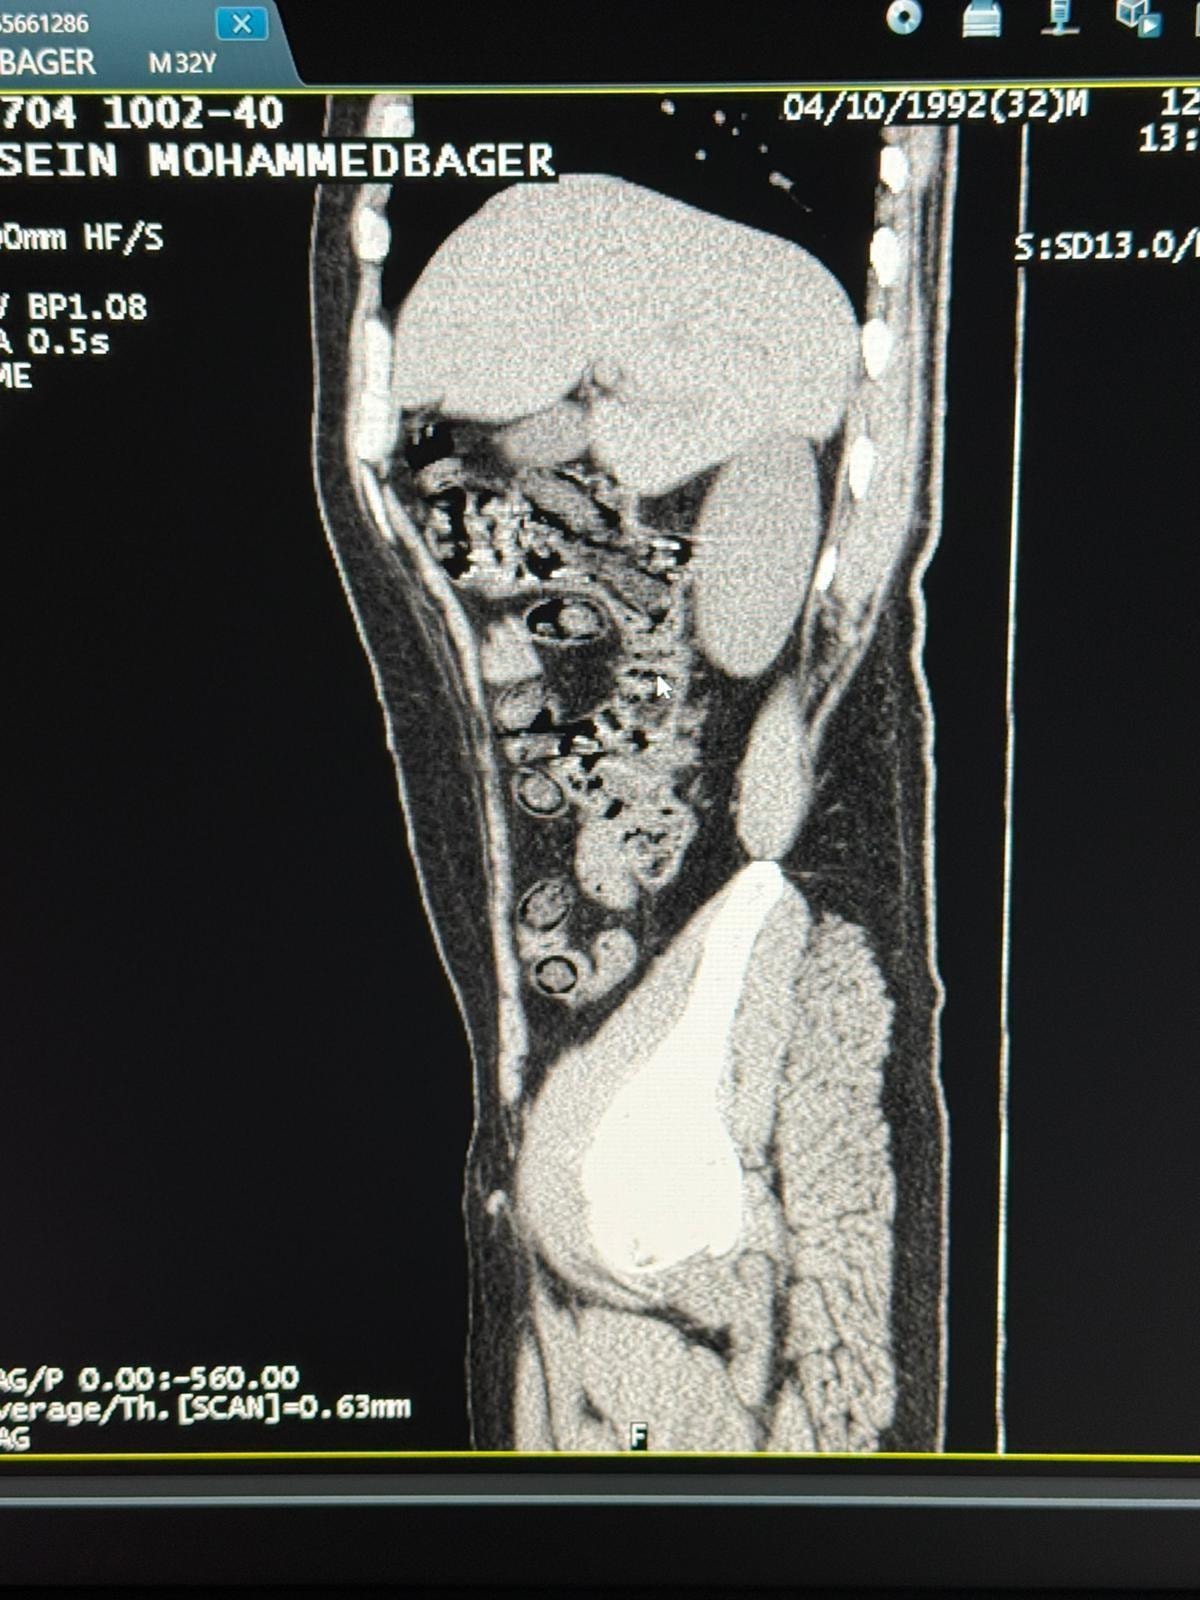

Hastanede yapılan iç beden muayeneleri sırasında çekilen tomografi görüntülerine göre uyuşturucu madde yuttukları tespit edilmiştir. Hastanede yapılan tespit sonrasında şahısların midelerinde toplam 94 adet kapsül içerisinde daralı ağırlıkları 928 gram gelen metamfetamin maddesi ele geçirilmiştir. Şüpheli şahıslar hakkında ‘uyuşturucu ve uyarıcı madde ticareti’ suçundan işlem yapılmak üzere Cumhuriyet Başsavcılığına intikal ettirilmiş ve çıkarıldıkları mahkemece tutuklanmışlardır.